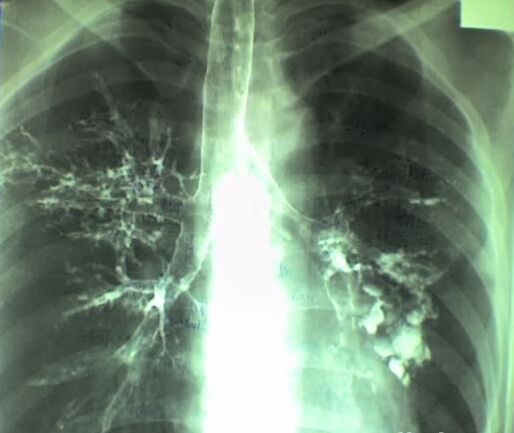

支气管扩张是一种常见的慢性支气管疾病。其基本病变是由于支气管及其周围肺组织的慢性炎症,使支气管管壁损坏变形和持久的扩张。本病多发生于青年和儿童,男性多于女性,可以由多种原因引起。

1、支气管感染和阻塞:支气管、肺脏的反复感染,支气管阻塞,导致支气管管壁损坏,变形和扩张。左下叶及右中叶多见。因左下叶支气管细长,受心血管的压迫,易致引流不畅和继发感染之故,右中叶周围有淋巴结颁,也易引流不畅,引起支气管扩张。

2、肺纤维收缩和胸膜粘连,使已受病变侵袭受损的支气管管壁被牵拉而发生扩张。如肺结核、肺脓肿、胸膜纤维化等。

3、先天发育缺损和遗传因素亦可引起支气管扩张,如巨大气管-支气管扩张症,可能是因支气管平滑肌软骨和弹力纤维发育不全,管壁结构薄弱和弹性较差而引起。肺囊性纤维化是由于末梢肺组织发育不良,小细支气管呈柱状,囊状扩张,支气管黏液腺分泌大量黏液,引起阻塞肺不张和继发感染,导致支气管扩张。